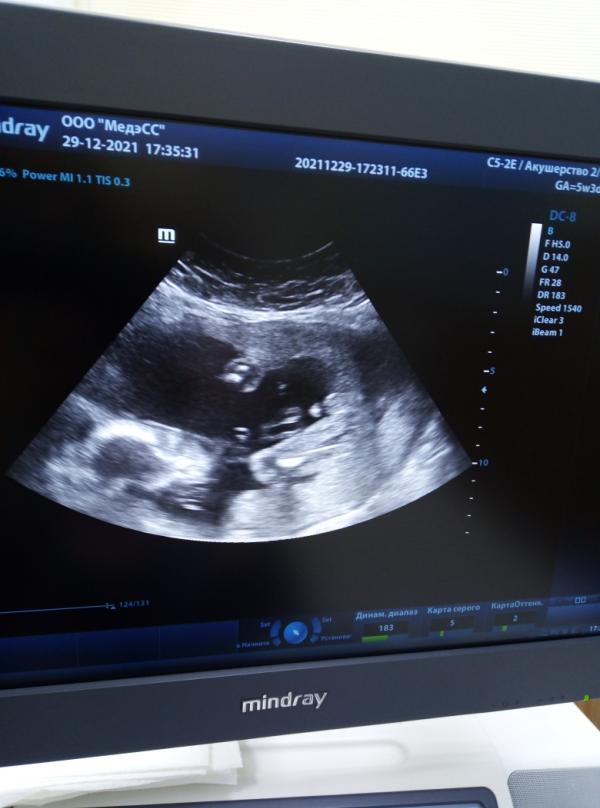

По этому фото можно определить пол? (догадается ли муж?)

Мне сказали мальчик, но как показать мужу и объяснить, что и как тоже не могу, по фото не понимаю

Ну я так понимаю огурчик который там есть это и есть мужское достоинство ))

Конееечно, видно пипирочку))

Если сомневаетесь, обведите в кружочек)